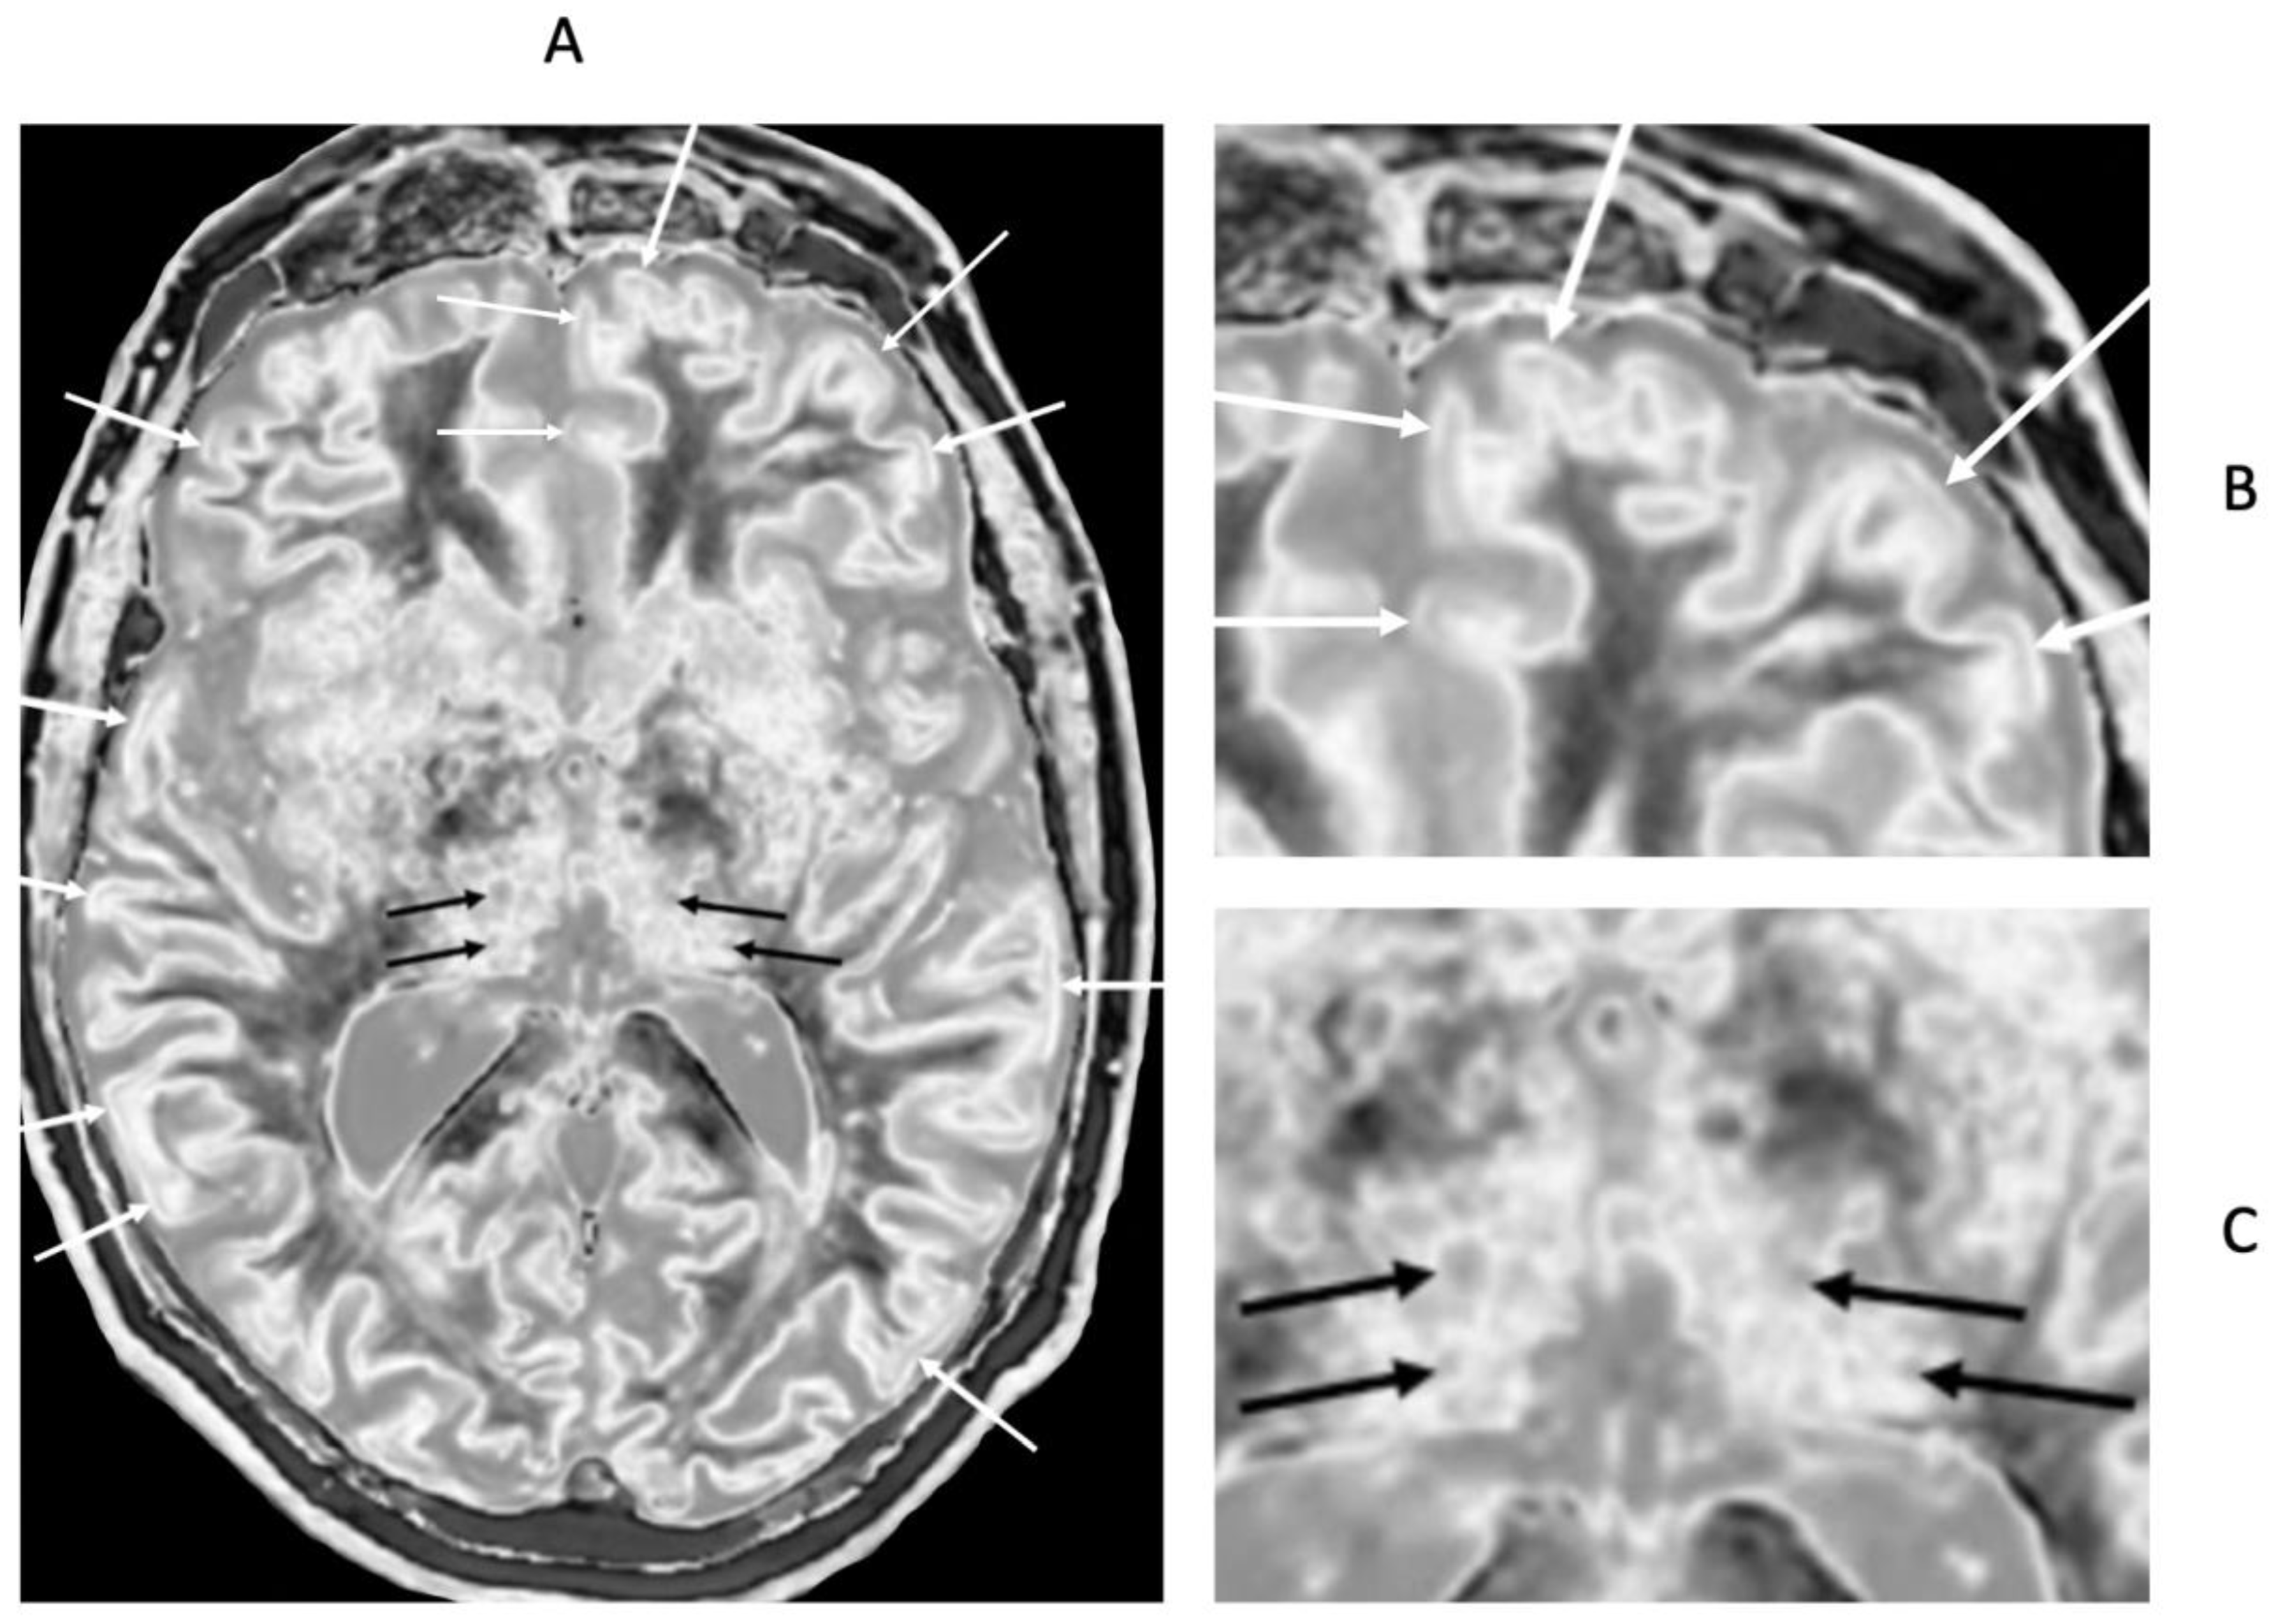

Focal lesions, as well as patchy white matter changes, may be seen in areas that appear normal on T

2-wFSE images in a patient in remission (

Figure 15) (compare with normal low signal appearance of normal peripheral white matter in

Figure 1B). In another case during a relapse, one lesion is seen on the T

2-FLAIR image in

Figure 16A (long arrow). This lesion is also seen in

Figure 16B (long arrow). There are an additional six lesions (small arrows) in

Figure 16B. Five of the lesions in

Figure 16B have high signal boundaries. This can be due to a large increase in T

1 in the lesion beyond the peak of the bipolar T

1-filter or a decrease in the abnormal T

1 in the lesion due to the presence of paramagnetic free iron. Two of the lesions with high signal boundaries shown in

Figure 16B have paramagnetic rim signs on the filtered susceptibility weighted images (arrows,

Figure 16C). The high signal boundaries seen on some MS lesions may be a sign of disease activity.

In addition, there are widespread abnormal areas in white matter which are only seen on the dSIR images (

Figure 16). These changes are typically bilateral, symmetrical and have an increased signal. They have the features of a whiteout sign (

Figure 16B) and to date have only been seen in patients with MS during a relapse.

Figure 16.

32-year-old female with MS during a relapse. T

2-FLAIR (A), synthetic narrow mD dSIR (T

1-BLAIR) (B) and filtered gradient echo (C) images. On the T

2-FLAIR image (A), one lesion is seen (long arrow). The surrounding white matter appears normal. On the T

1-BLAIR image (B), the lesion shown on the T

2-FLAIR image is seen with a high signal boundary (long arrow) as well as six other lesions four of which also show high signal boundaries or bubble signs (short arrows). Two of the five high signal lesions show paramagnetic rim signs on the filtered gradient echo image (arrows) in (C). In addition, most of the white matter in (B) is high signal corresponding to a high grade 4/5 whiteout sign [

1]. No whiteout sign is seen on the T

2-FLAIR image (A).